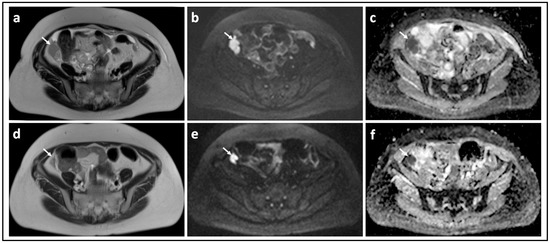

Figure 2.

Borderline versus malignant ovarian tumor: T2-W image (a) and corresponding b = 1000 s/mm2 DW-MRI (b) and ADC map (c) through the mid-pelvis in a patient with a mucinous borderline tumor of the left ovary. There is a large multiloculated cystic mass with no significant solid components (arrows). Two small foci of low signal in (b) show no evidence of diffusion restriction in c (arrowheads). In comparison, the T2-W image (d), b = 900 s/mm2 DW-MRI (e), and ADC map (f) in a patient with invasive high grade serous ovarian cancer show bilateral solid irregular ovarian masses (arrows) and linear peritoneal metastases [arrowheads], all of which show marked diffusion restriction.